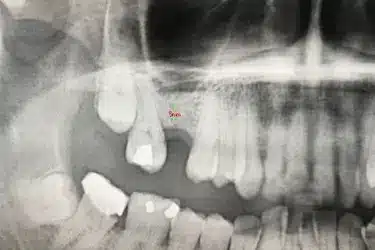

Antes del injerto de hueso dental solo había una altura de 5 mm para colocar el implante.

Para que el especialista pueda colocar un implante dental de forma estable y segura, es necesario una altura de hueso maxilar de al menos 8 – 10 mm.

El mismo día de la cirugía el implantólogo realiza una elevación del seno maxilar y posterior injerto de hueso dental artificial.

El odontólogo levanta la membrana del seno maxilar para introducir del material de relleno que aumentará la cantidad y la calidad del hueso del paciente.